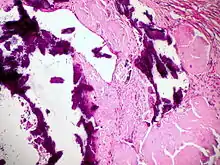

Amyloidosis, blood vessels, H&E

Amyloidosis, lymph node, H&E